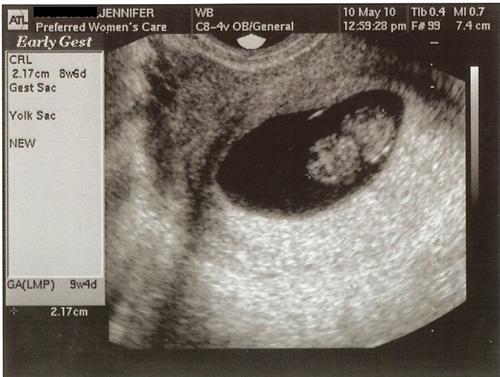

Well we saw our bean again and it has a head!!! I was a bad mom and couldn't tell which was the head and which was the butt..lol so if you are wondering it's to the left! lol But the heart beat is strong and we are so super excited. I am measuring on par with where I measured 2 weeks ago so I'm 8 wks 6 days with an EDD of December 11th!!!!

Image Attachment(s):

OH there it is! Thanks for posting the picture!